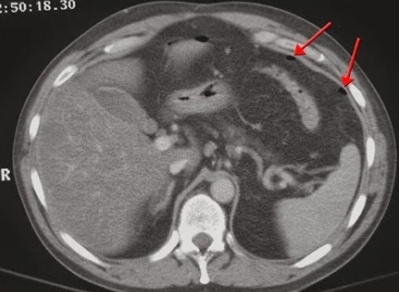

Đây là kỹ thuật hiện đại, cho phép đánh giá đồng thời tình trạng nhu mô các tạng và hình thái, bệnh lý của những mạch cấp máu đến tạng, các cuống mạch cấp máu và dẫn lưu trong các trường hợp dị dạng mạch và khối u.

● Khảo sát mạch các tạng: Nghi ngờ và đánh giá tình trạng huyết khối trong nhánh động mạch thân tạng và động mạch mạc treo tràng trên, cũng như hệ thống tĩnh mạch cửa, tĩnh mạch gan trong trường hợp tổn thương là khối u.

● Bước 4: Sau khi tiêm thuốc cản quang, chụp cắt lớp vi tính tầng trên ổ bụng với các lớp cắt ngang có độ dày lớp cắt lý tưởng là 2,5 mm, tái tạo các lớp cắt có độ dày 1mm. Chụp các lớp cắt ở thì động mạch sau khi tiêm từ giây thứ 25 - 30 để xem xét và đánh giá các tình trạng: mức độ giàu mạch của khối u; rối loạn tưới máu trong nhu mô ở những tạng đặc, đồng thời phát hiện tĩnh mạch dẫn lưu trong tổn thương dị dạng thông động - tĩnh mạch, Chấn thương tạng làm thuốc thoát ra ngoài lòng mạch.

● Bước 5: Chụp các lớp cắt ở thì tĩnh mạch sau khi tiêm thuốc cản quang từ giây thứ 60 - 70 để xem xét và đánh giá các tình trạng: mức độ thải thuốc của khối u, Chấn thương tạng. Chụp cắt lớp vi tính tầng trên ổ bụng với các lớp cắt ở thì muộn từ 3 - 10 phút.